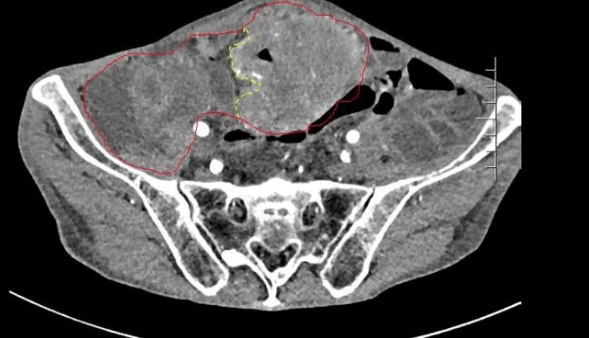

患者王大爺,男,72歲,發(fā)現(xiàn)腹腔腫物10余年,近兩年來(lái)患者雙下肢乏力、貧血,依靠間斷輸血維持著正常生活,出現(xiàn)頭昏,行動(dòng)困難,腹部疼痛及便血慕名來(lái)我院就診。入院后查體評(píng)估患者年齡大,體質(zhì)差,嚴(yán)重貧血,肺部感染及腸梗阻征象,腹部增強(qiáng)CT檢查提示腹膜后巨大腫瘤,長(zhǎng)徑超過(guò)30厘米,占據(jù)大部分腹腔,并可能存在雙原發(fā)腫瘤。

苗滿園腫瘤外科團(tuán)隊(duì)在麻醉科/手術(shù)室的緊密配合下為該患者進(jìn)行手術(shù),術(shù)中發(fā)現(xiàn)腫瘤巨大,幾乎占據(jù)了整個(gè)腹腔,從左側(cè)向右腹腔延伸,向上將肝、腎擠向膈下,向左將胃及小腸擠向左上腹,向下深達(dá)盆腔內(nèi),包繞下腔靜脈、腸系膜上動(dòng)脈等大血管及輸尿管,回盲部及回腸也受侵犯。手術(shù)難度巨大,風(fēng)險(xiǎn)極高。團(tuán)隊(duì)?wèi){借著高超的手術(shù)技能和精準(zhǔn)的手術(shù)預(yù)案沉著應(yīng)對(duì),迎難而上,應(yīng)用高頻電刀、超聲刀、切割縫合器等先進(jìn)設(shè)備,耗時(shí)近5小時(shí)為患者切除了巨大腹腔腫瘤,并聯(lián)合右半結(jié)腸切除,術(shù)中出血僅50ml。術(shù)后病理為腹膜后巨大平滑肌瘤+回腸腺癌。